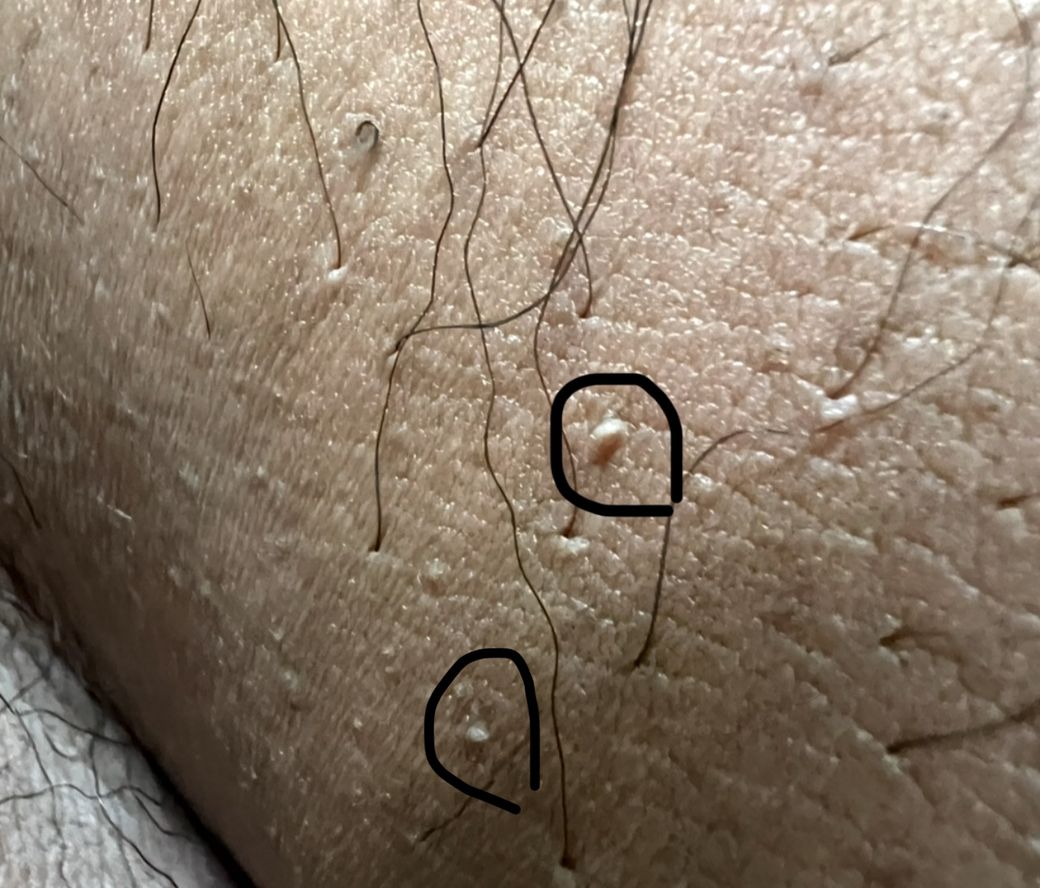

안녕하세요 성기와 사타구니 사이 마찰이 잦은 부분에 저렇게 동그라미 친 부분처럼 뭐가 올라와 있습니다 혹시 헤르페스 수포이거나 곤지름 구진 , 물사마귀 이런 병변일까요 구글에 검색을 해보니 물사마귀도 성병이라고 하기에 이렇게 덜덜 겁을 내며 여쭤봅니다 위에 말씀 드린 성병인지 아닌지 판단좀 해주시면 정말 감사하겠습니다ㅜㅜ 성병이 아니라면 단순 마찰로 인해 저런 병변이 생길수도 있는건지 궁금합니다 어떤 병변인지도 궁금하고요 답변해주시면 정말 감사하겠습니다

• 사진에서 보이는 병변은 표면이 매끈하고 피부색 또는 약간 흰색을 띠는 작은 구진 형태이며, 주변에도 유사한 병변이 산재해 있습니다. 염증성 홍반, 물집, 궤양 같은 소견은 보이지 않아 전형적인 헤르페스 양상과는 거리가 있고, 표면이 거칠고 증식하는 형태도 아니어서 곤지름과도 전형적인 모습은 아닙니다. 또한 병변의 분포와 형태를 고려하면 단일 감염성 병변보다는 피부 구조와 관련된 변화가 더 합당합니다.

임상적으로는 피지선이 표면에 드러나는 Fordyce spot과 같은 정상 변이 가능성이 가장 높으며, 일부는 모낭 주변의 경미한 변화가 동반되었을 가능성도 있습니다. Fordyce spot은 음낭이나 사타구니 인접 부위에서 흔히 관찰되며 감염성 질환이나 성병과는 관련이 없습니다. 물사마귀의 경우 중심 함몰이 더 뚜렷하고 점차 개수가 증가하는 경향이 있는데, 현재 사진은 그 전형성과는 다소 차이가 있습니다.

따라서 현재 소견만으로는 성병 가능성은 낮고 치료가 필요 없는 정상 범주의 병변일 가능성이 높습니다. 다만 병변이 점차 커지거나 개수가 증가하거나, 표면이 울퉁불퉁해지는 변화가 생기면 곤지름과의 감별을 위해 진료가 필요하며, 통증이나 분비물 같은 새로운 증상이 동반되는 경우에도 확인이 필요합니다.